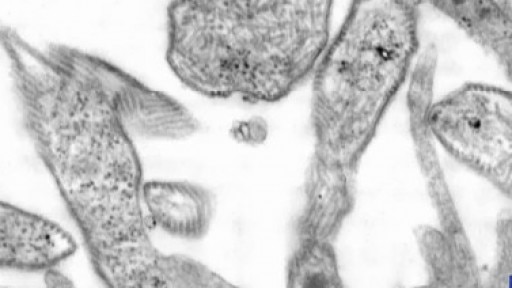

Two outbreaks of mumps are currently being investigated in Central Texas. Dr. Kumar has tips to avoid getting sick.